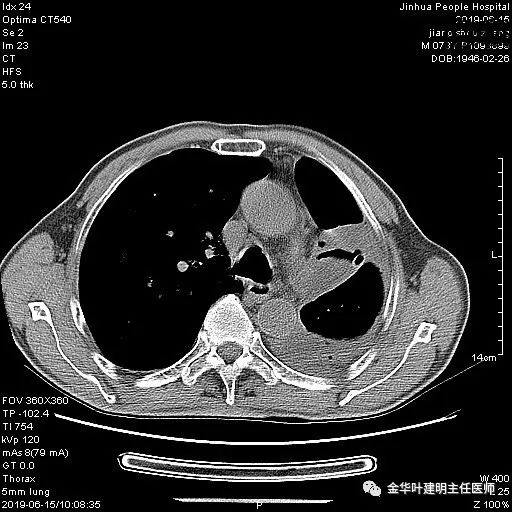

以上是肺窗表现,下面为纵隔窗影像:

6.15上午:24小时胸管引流出血性液250ml;复查胸部CT示: